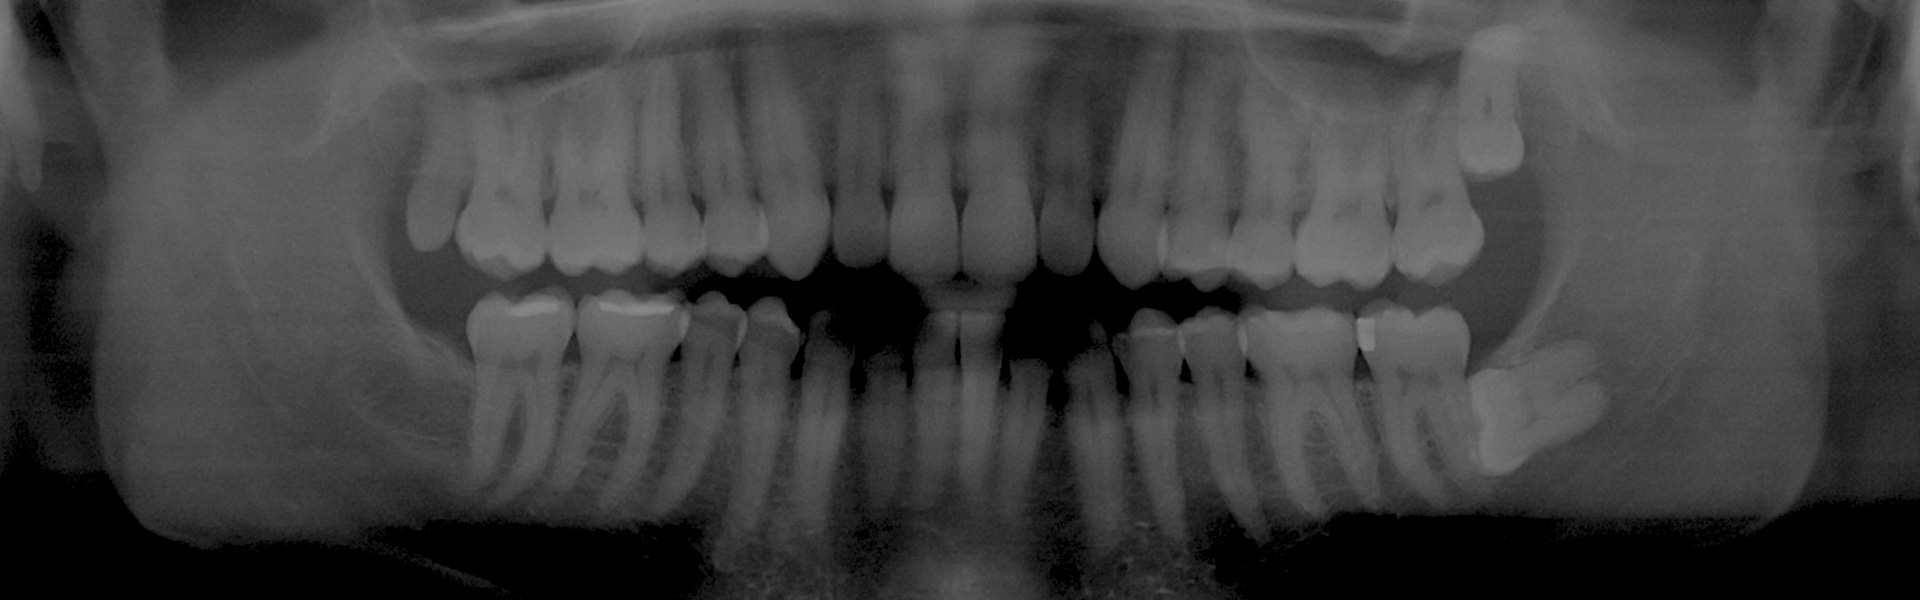

Wisdom Tooth Extractions